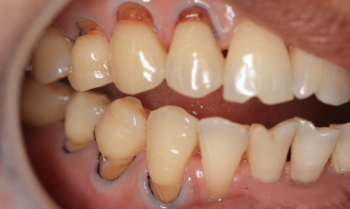

三 牙周病导致的牙龈肿痛

1、牙齿遇冷热酸甜疼痛,去除刺激物质后,疼痛消失

2、牙齿持续疼痛个好几天,吃了消炎药会见效,过段时间还会痛

3、牙齿疼痛且伴有红肿、松动,多伴有食物嵌塞症状,吃东西困难,严重甚至周身不适

如果上述症状否和的话,那么建议您来院拍摄全景片检查。进行第一步,超声波洁牙去除牙齿表面牙菌斑和牙结石等有害物质,消退牙龈炎症;第二步,龈下刮治:把牙龈下方的牙结石和牙周袋内的炎性肉芽组织清除,有效的治疗消除牙周炎症。第三步,牙周护理:使用进口派丽奥药物对牙龈进行安抚和护理,消炎保护牙龈。如果牙周疾病较严重也可以使用牙周治疗进行治疗和恢复。》》》点此咨询了解施尔美无痛口腔51项就诊细节服务!